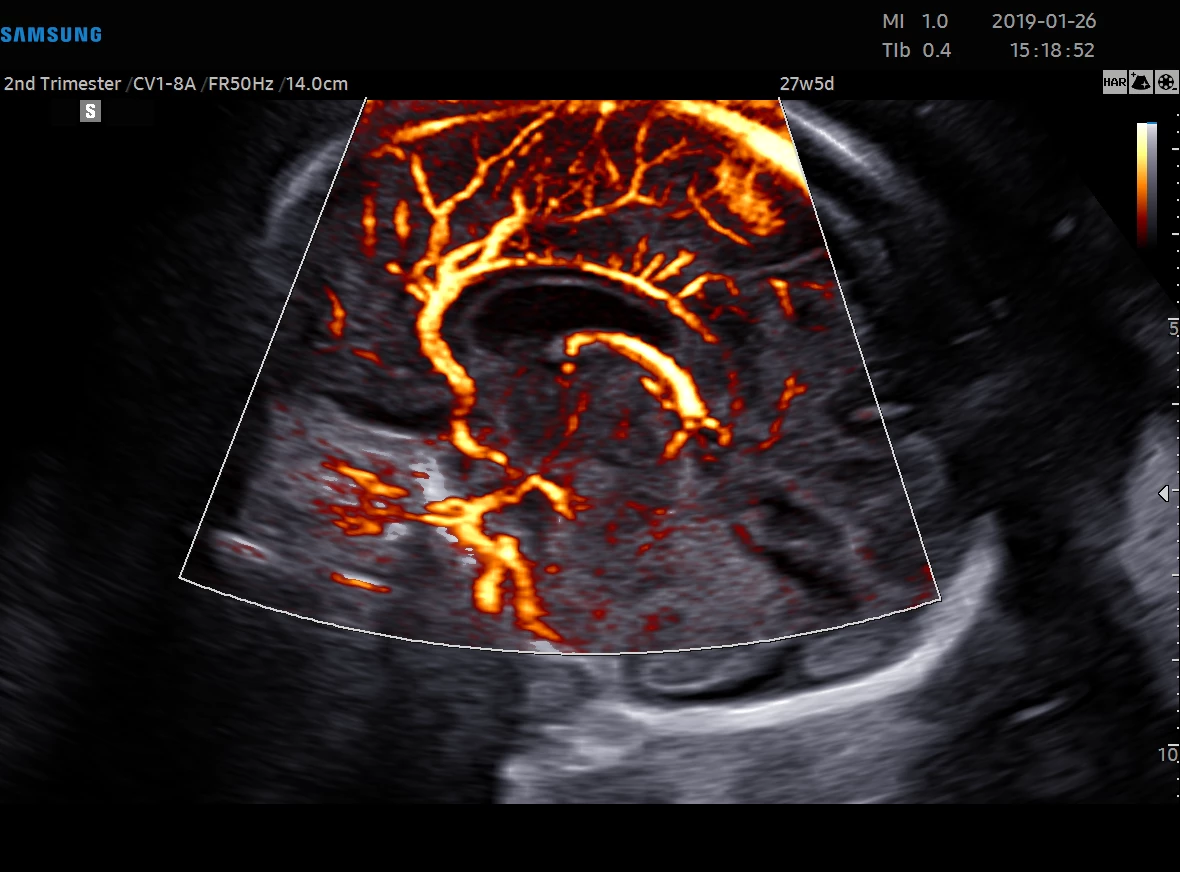

Diagnostykę obrazową przeprowadzamy z wykorzystaniem sprzętu Samsung HERA W9. To najnowszy aparat klasy premium – z kompletem głowic USG wysokiej rozdzielczości w tym głowicą USG 3D/4D. Doskonała jakość obrazu przekłada się na wiarygodność wyników.

• USG ginekologicznym i w czasie ciąży wtym 3D/4D.

Ponadto jesteśmy w stanie zmierzyć przepływy w naczyniach u kobiet ciężarnych oraz płodu.